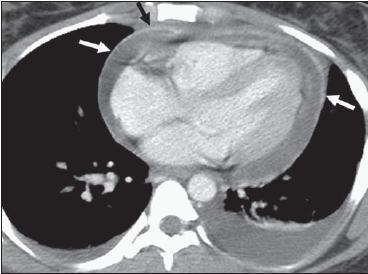

Pleuropulmonary involvement is often an early finding, but it is rarely the presenting manifestation of RA.7,8 Pleural effusion can appear at any point in the course of RA and may or may not be associated with flares of joint symptoms (Figure 1).9 Several causes of rheumatoid pleural effusion have been proposed, including chronic inflammation and fibrosis; the high protein content of the fluid, which leads to increased fluid retention in the pleural space; and the rupture of subpleural nodules with localized inflammation and fibrosis, which leads to capillary leak and obstruction of lymphatic drainage.9,10

Figure 1 – Pleural and pericardial effusions secondary to serositis were found in a 25-year-old woman with rheumatoid arthritis. The transverse CT image after administration of intravenous contrast demonstrates enhancement of the pericardium (arrows), which is typically seen with exudative effusions.